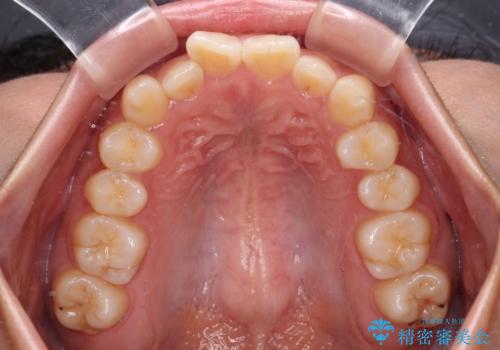

デコボコと捻れて前に飛び出した歯列 抜歯矯正でスッキリした口元に

- 前歯のデコボコと口元の突出感を気にして来院された患者様です。

非抜歯矯正ではデコボコを解消することでより口元が突出してしまうため、上下左右の小臼歯4本の抜歯を行い、ワイヤー装置による矯正治療を行うこととしました。